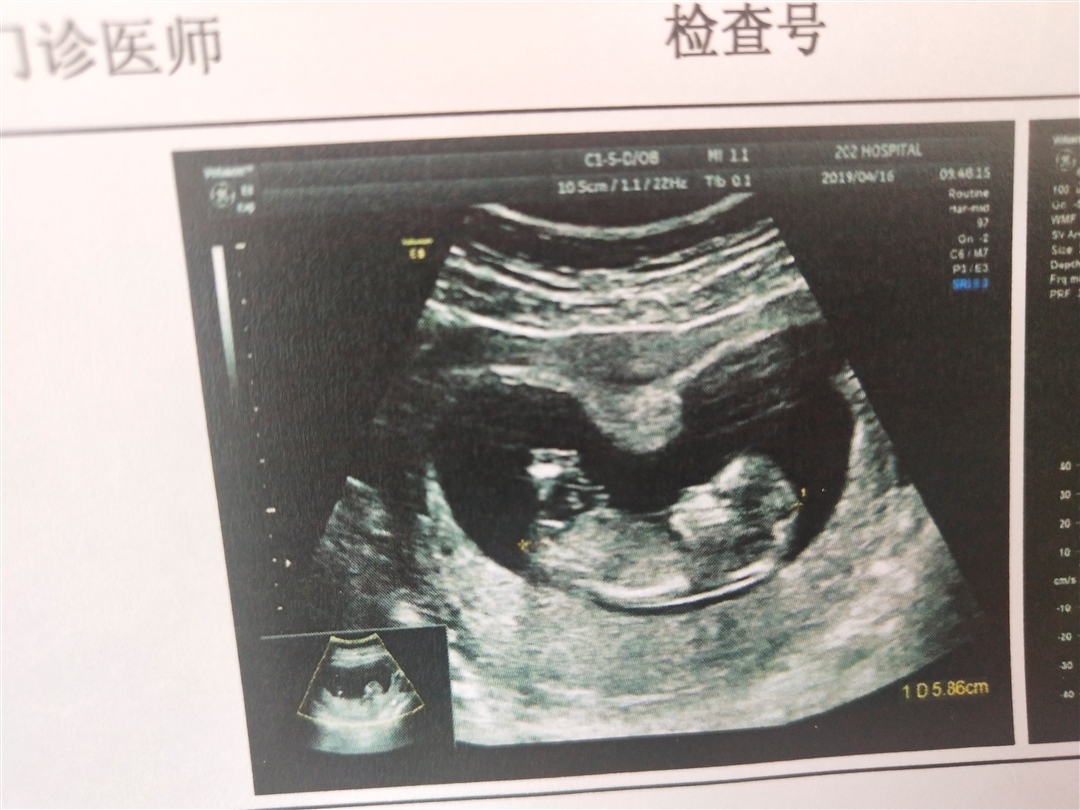

孕7周+2天

哈哈,我觉得有点吓人

星 儿🇨🇳[帖主]:哈哈哈 脑袋好大